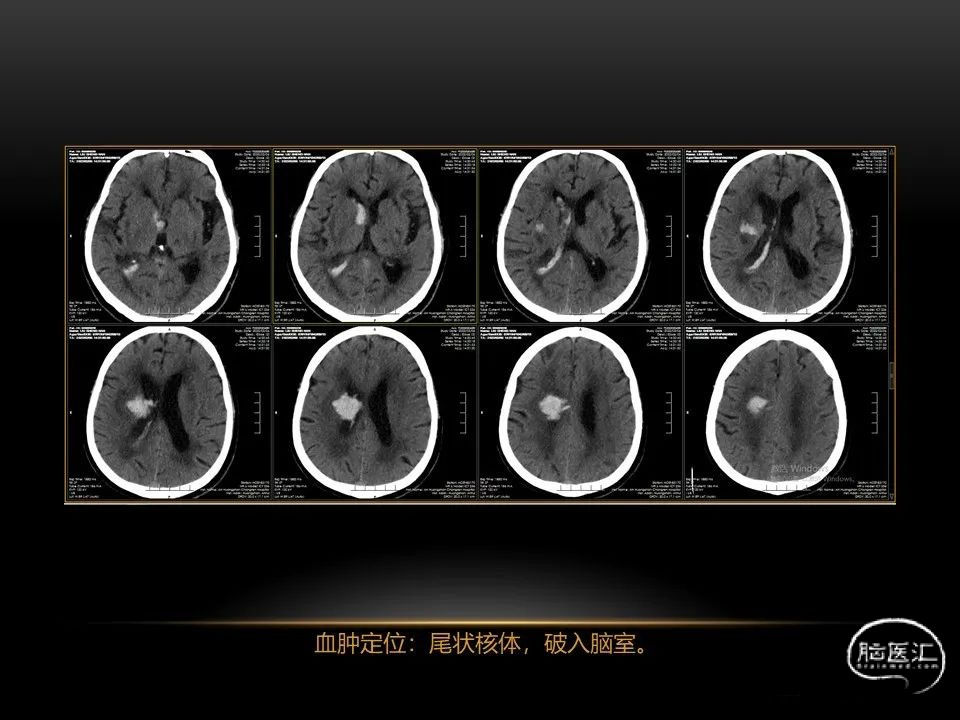

自发性脑出血临床上很常见,不同原因有特征性的出血部位。例如:基底节出血和丘脑出血大多是高血压性脑出血;脑叶出血,特别是多次复发的脑叶出血多见于老年人的脑血管淀粉样变。

自发性脑出血不仅仅累及内囊后肢才会出现偏瘫及偏身感觉障碍,病变累及大脑脚或辐射冠同样有可能有类似症状和体征。内囊、辐射冠、大脑脚等结构之间是延续的,只是不同区域不同名称而已。定位诊断需要对解剖结构概念清晰,读片准确辨认,灵活掌握。